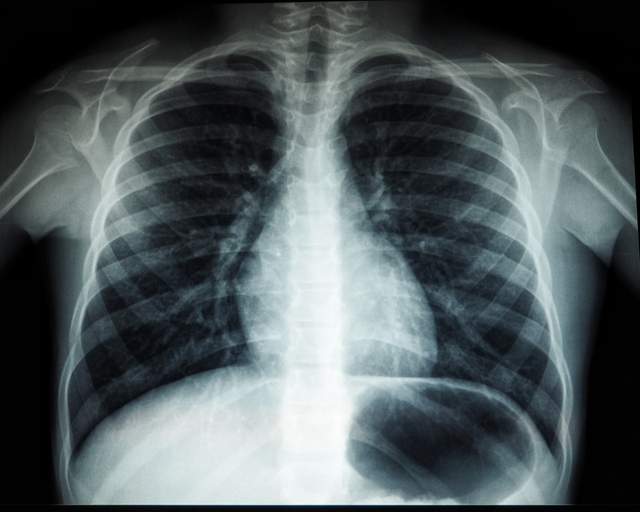

2292465.jpgГеномний аналіз показав, що більшість мутацій, з якими пов'язаний рак легень у некурців, не пов'язані з зовнішніми чинниками. Повний текст новини